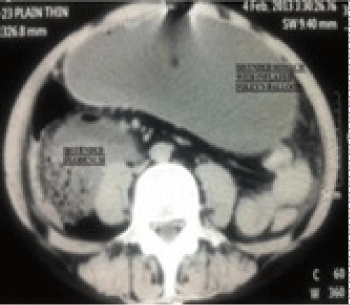

Figure 1: CT abdomen showing distended stomach, duodenum & tip of

catheter seen in stomach along with inflated balloon.

On examination, he was conscious, awake and well oriented. There was no significant finding on examination of cardiac and respiratory systems. The abdomen was distended. Nasogastric tube and per urethral Foleys catheter were in situ with no urine in bag. Interestingly SPC showed stomach contents. Peripheral and central venous catheters were already inserted earlier. Heart rate was 120 beats per minute and blood pressure was 90/60 mm of Hg. Platelet count was 60,000/cmm. All other laboratory investigations were normal. Ultrasonography report was suggestive of duodenal obstruction with SPC wrongly inserted into stomach. There was moderate amount of free fluid in pelvis suggestive of perforation with collapsed urinary bladder. Same findings were noted on CT abdomen report. Thus the indication of insertion of SPC due to absence of urine after urethral catheterization was wrong as the patient had anuria probably due to obstruction.